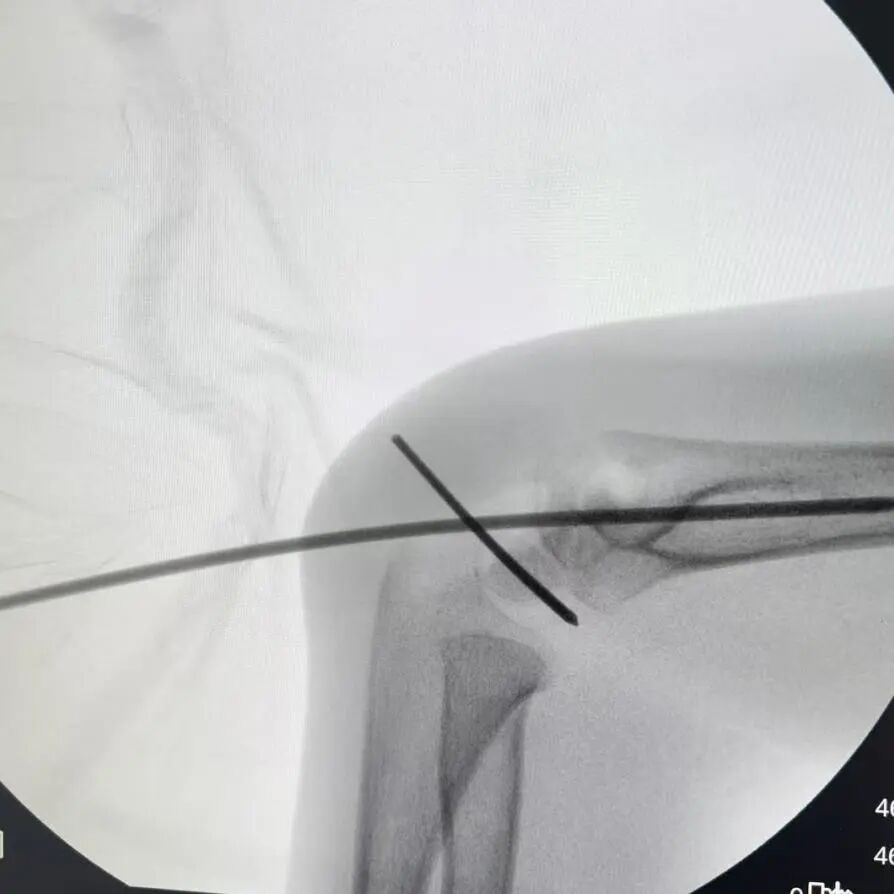

“孩子现在是最重要的初二,落下一周课就跟不上了!”小廖妈妈刚带孩子入院时,最焦虑的就是学习问题。让她意外的是,医院骨伤科手外·儿骨·烧伤整形组团队当即开通“儿童骨折急诊绿色通道”,仅用18小时就完成了术前检查、评估和桡骨远端骨折闭合复位经皮固定术。

同样“抢时间”的还有小罗和小周的治疗:4岁小罗9月15日深夜入院,10小时后顺利手术;7岁小周同一晚受伤,也在10小时内完成肱骨髁上骨折闭合复位经皮固定术。6岁小郑更是创下“4小时极速手术”纪录——早晨7点40分受伤,8点多入院,11点多手术结束,当天下午就能躺上网课。

“我们的目标是‘24小时内完成急诊手术’,尽量让孩子少耽误一节课。”骨伤科手外·儿骨·烧伤整形组主任陈孝均教授介绍,为了实现这个目标,团队制定了专属流程:孩子入院后,急诊优先开具检查单,放射影像科快速出片;骨科医生同步评估病情,确定手术方案;麻醉科提前做好准备,只要术前检查合格,立刻安排手术——哪怕是深夜或周末,团队也随时待命。